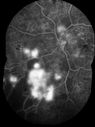

Proliferative Diabetic Retinopathy and Vitreous Hemorrhage - FA shows leakage of dye from NVE504 viewsApr 25, 2013

Proliferative Diabetic Retinopathy and Vitreous Hemorrhage - FA shows leakage of dye from NVE465 viewsApr 25, 2013

Proliferative Diabetic Retinopathy and Vitreous Hemorrhage - FA shows leakage of dye from NVE480 viewsApr 25, 2013

Proliferative Diabetic Retinopathy and Vitreous Hemorrhage - FA shows leakage of dye from NVE643 viewsApr 25, 2013

Proliferative Diabetic Retinopathy and Vitreous Hemorrhage - FA shows leakage of dye from NVE682 viewsApr 25, 2013

Proliferative Diabetic Retinopathy and Vitreous Hemorrhage - FA shows leakage of dye from NVE698 viewsApr 25, 2013

Proliferative Diabetic Retinopathy and Vitreous Hemorrhage - FA shows leakage of dye from NVE558 viewsApr 25, 2013

Proliferative Diabetic Retinopathy and Vitreous Hemorrhage - FA shows leakage of dye from NVE468 viewsApr 25, 2013

Proliferative Diabetic Retinopathy and Vitreous Hemorrhage - FA shows leakage of dye from NVE499 viewsApr 25, 2013